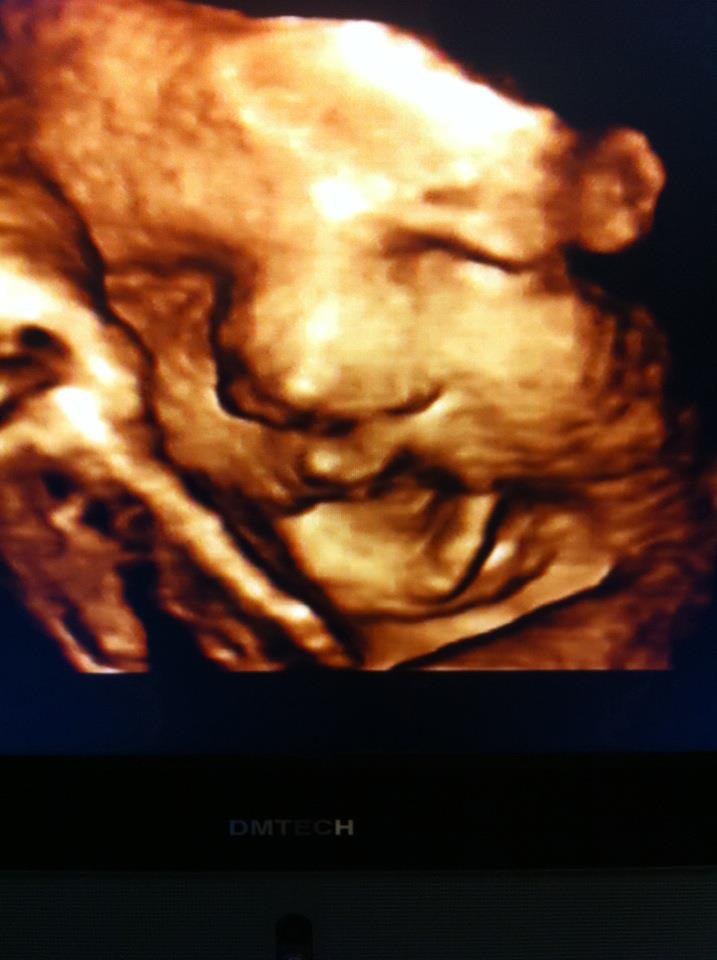

3: Storm

4: lillebror Sylvester

... Det tredje billed er for at sammenligne med vores den mindste, syntes de ligner hinanden meget godt